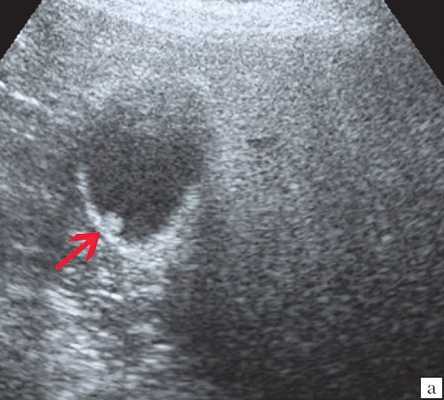

Рис. 3. Киста правой доли печени

Из обследованных детей у 19 обнаружены эхинококковые кисты печени. Для эхиноккокозов печени ультразвуковая картина была достаточно характерной — определялись отдельные кистозные полости размером от 2-3см до 10-12см в диаметре, с четкой капсулой. Стенка кисты состояла из фиброзной и хитиновой оболочек, содержимое — жидкостное. В некоторых случаях определялись дочерние пузыри из зародышевого слоя. Эхинококкоз печени в 3-х случаях сочетался с эхиноккокозом легких; у 1-го — почек. Таким образом, эхиноккокоз внутренних органов достоверно выявлялся при ультразвуковом обследовании.